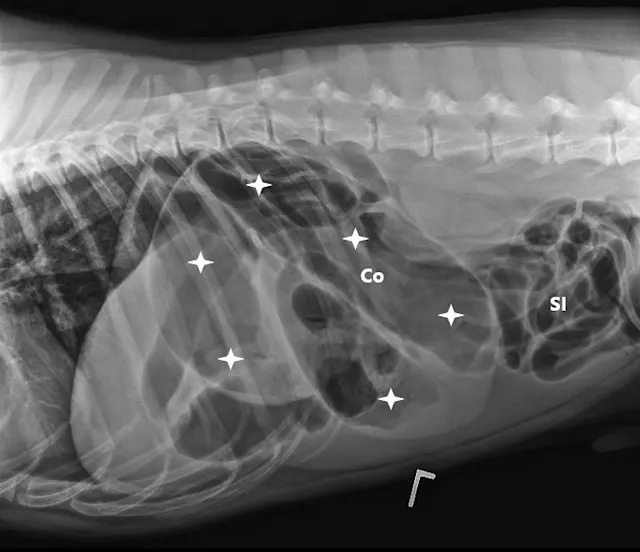

FIGURE 1A

Right lateral (A), left lateral (B), and ventrodorsal (C) abdominal radiographs demonstrating marked dilation of a single bowel loop with gas and amorphous material in the right cranial abdomen, suspected to be the colon (arrows). Caudal displacement of the small intestines (SI) can also be seen. The descending colon (Co) is poorly visualized.

Three-view abdominal radiographs revealed a single bowel loop markedly dilated with gas and amorphous material in the cranial abdomen thought to represent the colon due to its unusual position (ie, could not be tracked from caudal to cranial aspect on lateral radiograph; Figure 1). The small intestines were displaced caudally with no evidence of ileus (ie, gas filled but normal and uniform in diameter), and the descending colon was not fully visualized.